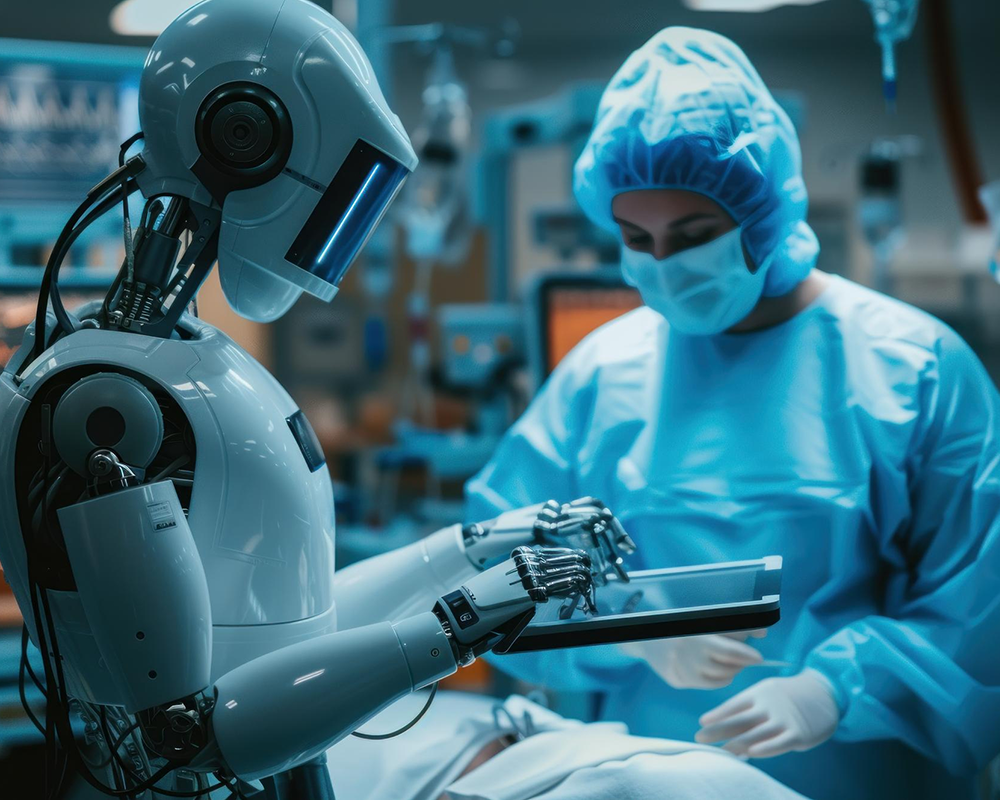

रोबोटिक सर्जरी: क्या है और कैसे मदद करती है

आज के समय में चिकित्सा जगत तेजी से आगे बढ़ रहा है। नई-नई तकनीकों की मदद से इलाज न केवल आसान हो गया है बल्कि मरीजों को जल्दी ठीक होने में भी मदद मिल रही है। इन्हीं आधुनिक तकनीकों में

रोबोटिक सर्जरी: क्या है और

आज के समय में चिकित्सा जगत तेजी से आगे बढ़ रहा है। नई-नई तकनीकों की मदद से इलाज न केवल आसान हो गया है बल्कि मरीजों को जल्दी ठीक होने...